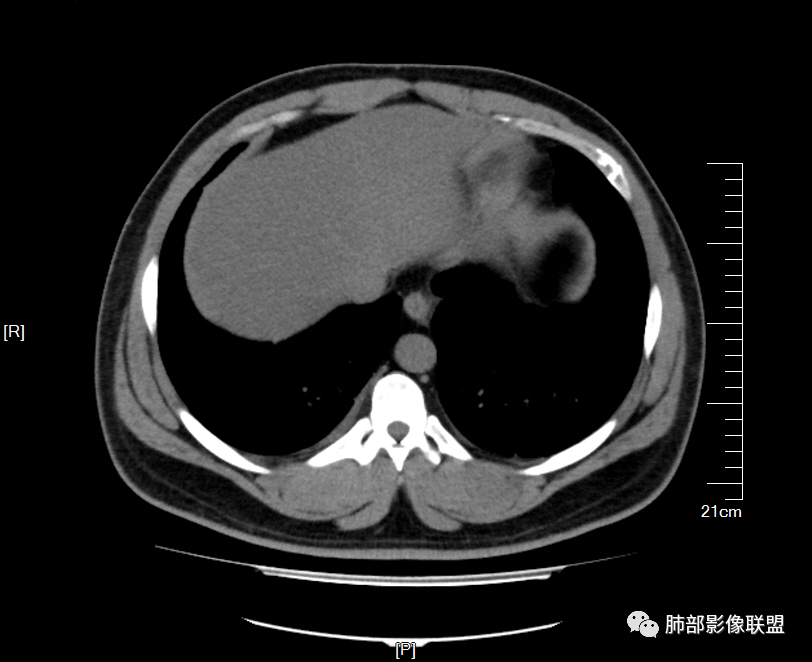

男32岁。既往曾发现血肌酐升高.此次因左足痛6天入院。有痛风、高血压病史。两肺弥漫性的病变,小片状或者结节状为主病变,小叶中心分部为主,边界不清。心影比较饱满,肝实质密度均匀的降低。考虑为肝损害的影像学改变。综合考虑多功能脏器的损害,肺部损害肺泡炎?肺水肿?或病毒性的肺炎?

少量积液,脂肪肝

中轴间质增厚,小叶间隔增厚,小叶内间质增厚,部分重力作用,双侧对称,胸水,按理淋巴道回流受阻有